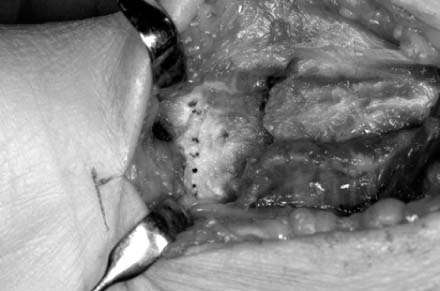

Fig. 9

The pronator quadrates is elevated from the lateral edge of radial orign.

Fig. 9 The pronator quadrates is elevated from the lateral edge of radial orign.